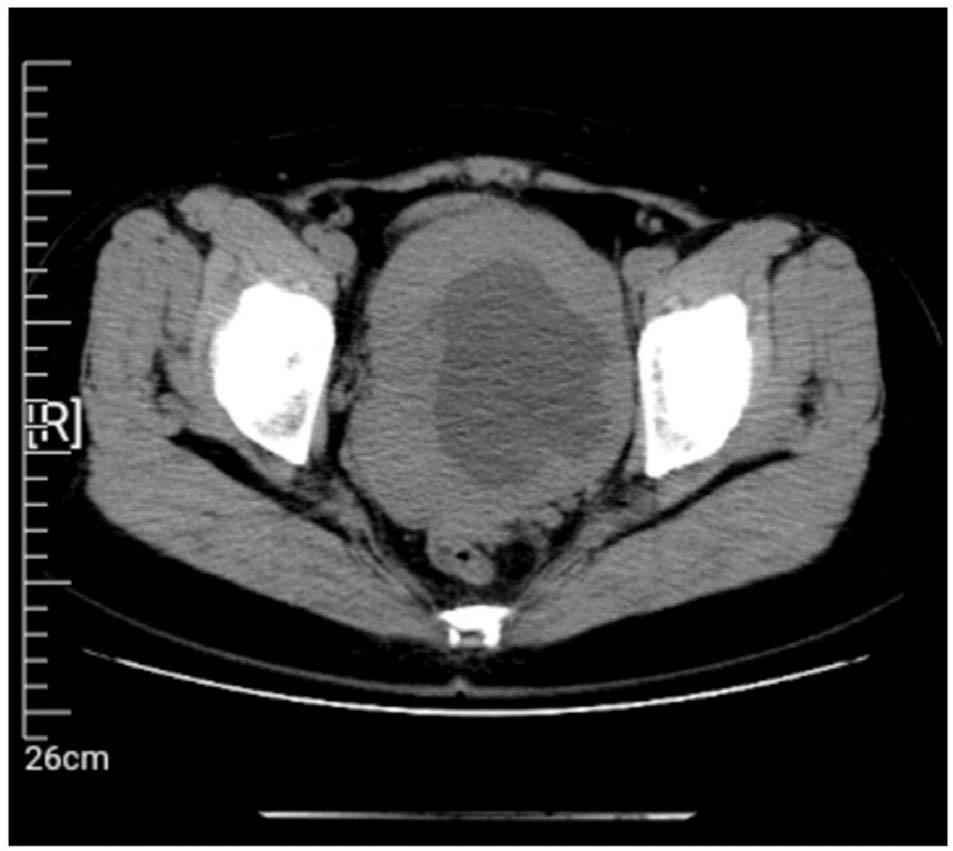

No regular ultrasound reexamination was performed until April 2021, and the results showed an enlarged and morphologically abnormal uterus, a mixed uneven echogenic mass at the posterior wall of the uterus (101 mm × 85 mm, with 7 mm thick endometrium), and a dark cyst (109 mm × 93 mm) in the right adnexal area with dense punctate echo, suggesting suspected uterine myoma with liquefaction and a suspected chocolate cyst. Abdominal computed tomography showed lesions in the pelvis and uterus (Figure 1). A pelvic magnetic resonance imaging examination suggested a suspected myoma cyst with malignant potential in the uterus and a suspected cystadenoma in the right adnexal area (Figure 2).

Figure 1

Pelvic computed tomography image showing an unclear defined 11 cm pelvic mass without further abnormalities.